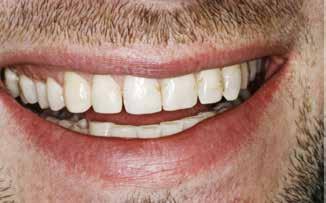

Fig. 1. 40-årig sund og rask mand møder bekymret for sine slidte tænder. Klinisk ses frakturer og substanstab langs incisalkanterne på overkæbetænderne.

Fig. 1. A 40-year-old healthy man is concerned for his worn teeth. Clinically, fractures and loss of tooth substance are observed at the incisal edge of the upper front teeth.